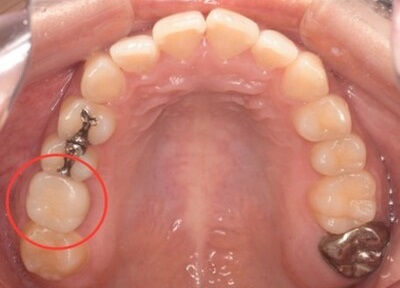

移植12ヶ月後の口腔内写真

移植12ヶ月後のレントゲン

移植12ヶ月後。セラミッククラウンで歯冠を修復した。

デンタルX線写真では透過像もほぼ消失している。